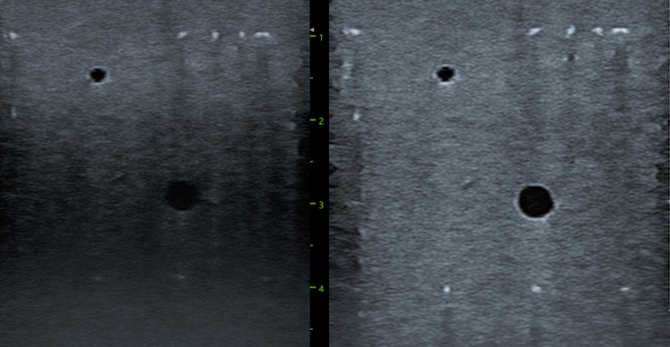

全域聚焦技术 支持全场高分辨率

更清晰的影像质量